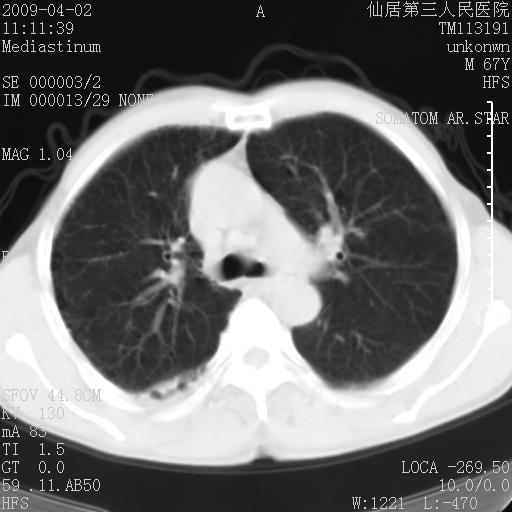

患者老年男性,乏力畏寒来诊,摄胸片示右下肺感染性病变,抗炎两周后复查胸片,无好转有进展。

后做ct平扫表现如下:

考虑右肺炎症可能性大,不除外细支气管肺泡癌

是否还要考虑肺间质纤维化,建议hrct扫描。

考虑间质性肺炎。

病灶呈蜂窝征,纵隔多个淋巴结肿大;肺泡癌需考虑

考虑双肺间质性改变(间质纤维化?)伴右肺下叶感染。